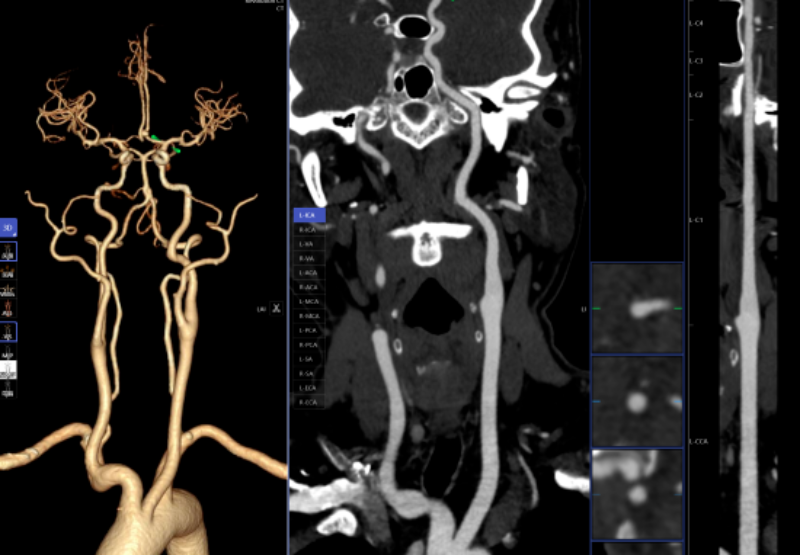

血管診斷、腦血管灌注成像

頭頸部CTA、冠狀動脈CTA、肺動脈CTA及肢體CTA是一種無創(chuàng)、低風險、快速的檢查方法,能夠清晰識別血管狹窄、畸形或斑塊,明確病灶與周圍正常組織的位置關系,為治療方案的制定提供有力依據(jù),能提高患者生存率,縮短高危患者急救救治時間。

以往,放射科醫(yī)生進行頭頸部CTA和冠狀動脈CTA重建后處理,需要醫(yī)生應用工作站手動處理,耗時約20-30分鐘。而AI人工智能輔助診斷系統(tǒng)通過計算機視覺和深度學習技術,僅需5-10分鐘即可完成影像重建的后處理計算,一鍵生成精準的三維重建圖;系統(tǒng)還能自動標記血管名稱、快速判斷斑塊性質(zhì),并根據(jù)最新指南對狹窄程度進行分級診斷等,幫助醫(yī)生快速定位病變節(jié)段,準確分析斑塊類型及狹窄程度;對腦血管灌注成像進行快速重建和診斷,大幅縮短患者等候檢查和獲取診斷報告的時間。